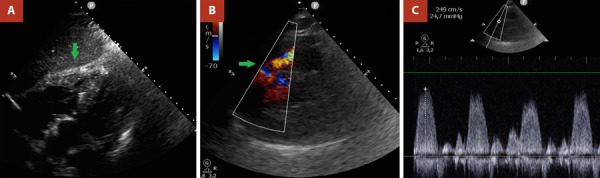

We present the case of a 42-year-old male patient with a history of bilateral lung transplantation and chronic graft dysfunction. The patient presented to the adult emergency department due to acute heart failure. During his stay in the emergency room and in outpatient follow-up, cardiac multi-imaging led to the diagnosis of double-chambered right ventricle with associated hypertrophic cardiomyopathy. Given the presence of advanced lung disease and poor adherence to immunosuppressant medication as well as clinical follow-ups, the patient was deemed unsuitable for re-lung transplantation. The optimization of his immunosuppressive medication was prioritized, and beta-blockers were added as part of the treatment for dynamic right ventricular outflow obstruction. He was referred to pulmonary rehabilitation, currently showing a partially favorable evolution to functional class II.